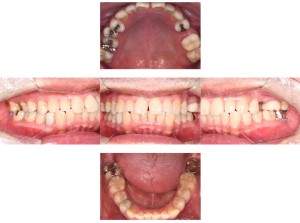

インプラント治療の症例1

レントゲン写真

- 透過像

症例写真-1

- Befor

- After

症例写真-2

- 途中経過

| 年齢 | 50代・男性 |

| 主訴 | 右下歯が疼く |

| 治療内容 | ・右下6番インプラント ※1:FGG(遊離歯肉移植術)とは、足りない歯ぐきを上顎から上皮を切り取り移植する外科手術 |

| 治療費 | 合計:902,000円(税込) ■内訳 |

| 治療期間 | 9ヵ月 |

| 治療方針 | 右下の当該歯は歯根破折により保存不可能と診断しました。歯周疾患も伴っていたため抜歯後に骨吸収※1が大きく起こることが予測できました。チタンメッシュ併用骨再生誘導法(GBR※2)を選択しインプラント埋入と同時に行い自然な歯槽骨のラインを再現しました。またGBRを行う際にインプラント辺縁の付着歯肉の減少が起こる為、遊離歯肉移植術(FGG※3)を行い清掃性を考慮した形態に仕上げました。 ■治療方針の解説 治療した右下の歯をレントゲンで撮影したところ根本の部分に黒く写る箇所があり「根尖性慢性周囲炎※1」と診断。また歯周病も進行していました。 ※1 骨吸収・・・歯槽骨という歯を支える骨がなくなっていくこと |

| 担当者所見 | 主訴の右下だけでなく歯茎の腫れ、発赤があり不良補綴や不良充填など他にも治療箇所が多数ありました。プラークコントロールが不良であった為まずはブラッシング指導を行いセルフケアの重要性を理解していただくところからスタートしました。 右下6番の歯はインプラント治療を行なった結果審美的にも機能的にも患者様の満足を得ることができました。骨造成と歯肉移植も行なった為インプラントを支える十分な歯周組織の獲得ができたと思っております。 |